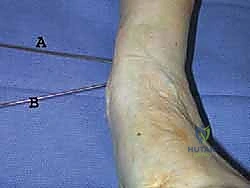

2. الشق الجراحي والوصول الآمن

يُجري الدكتور هطيف شقاً جراحياً دقيقاً في الجزء السفلي من الساق. بفضل خبرته في الجراحة الميكروسكوبية والتشريح الدقيق، يتم إبعاد الأوتار، والأوعية الدموية، والأعصاب الحساسة بعناية فائقة لحمايتها من أي ضرر.

باستخدام أدوات قطع عظمية دقيقة جداً (مناشير جراحية متأرجحة)، وتحت توجيه جهاز الأشعة السينية المباشر في غرفة العمليات (C-arm)، يتم إحداث القطع في عظم الظنبوب في المكان المخطط له مسبقاً، مع الحفاظ على جزء بسيط من القشرة العظمية في الجهة المقابلة لتعمل كمفصلة (Hinge).